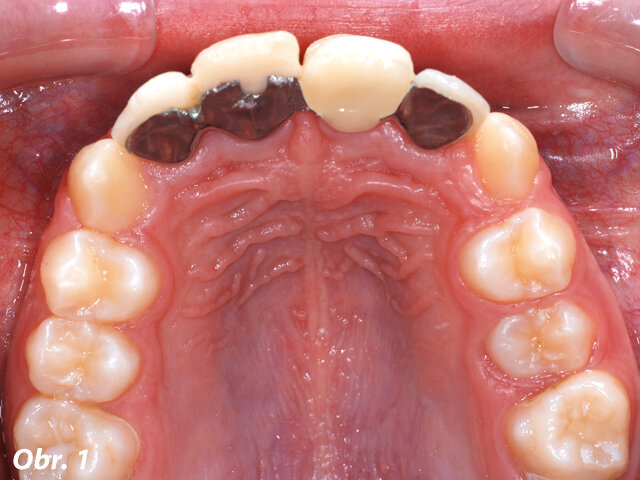

V 10 letech pacientka utrpěla trauma frontálních zubů s avulzí a replantací centrálních řezáků (zuby 11 a 21, dle značení FDI). Navzdory všem snahám nebylo možné zachovat zub 21. Předchozí zubní lékař tento zub nahradil metalokeramickým adhezivním můstkem (Marylandský můstek) (obr. 1 a 2). Naneštěstí byla v průběhu terapie potvrzena infaustní prognóza u zubu 11 – ten musel být extrahován během ortodontické léčby. Za účelem nahrazení obou centrálních řezáků byl zhotoven provizorní můstek s umělou gingivou, který byl připevněn na fixní ortodontické aparáty (obr. 3).

Obr. 1: Situace před ortodontickým ošetřením – adhezivní můstek s náhradou zubu 21